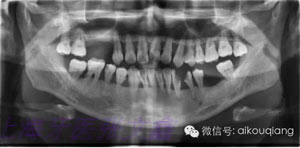

下面這張X光片是比較典型的牙周炎的X光片,該患者全口所有的牙齒都呈現(xiàn)出2~3度的松動。患者現(xiàn)在感覺無法用牙齒咀嚼。坦白地講,牙周炎發(fā)展到這種程度,很多時候醫(yī)生也束手無策了。為了保留更多的牙槽骨,醫(yī)生會不得不拔掉那些嚴(yán)重松動的牙齒。

4.jpg